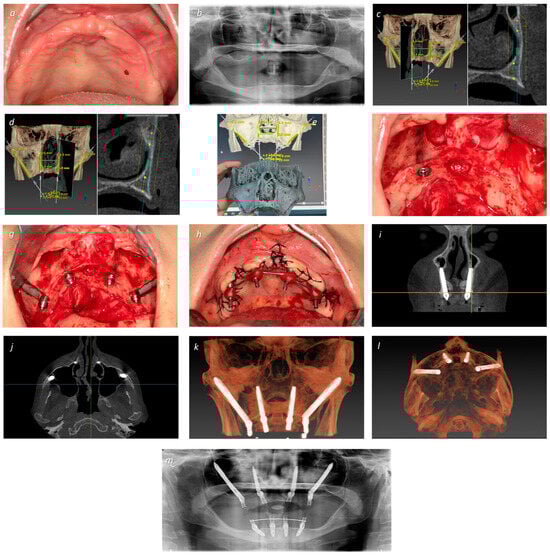

| 1 | EM 0° 5 × 40 | S 4 × 8.5 | T 3.75 × 22.5 | EM 0° 5 × 40 | 66 | F | 3 | I | NG | +50 |